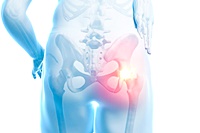

8. 고관절 점액낭염

고관절 주변의 점액낭에 염증이 생겨 통증을 유발합니다. 잘못된 자세나 갑작스러운 운동이 주된 원인입니다.